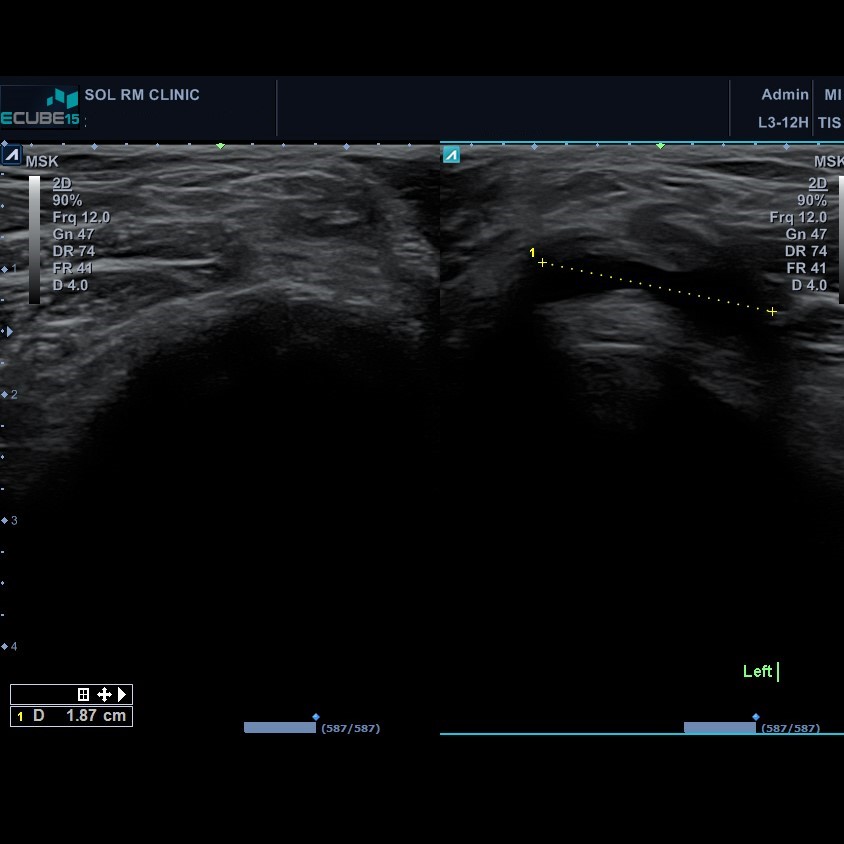

36세 남자 환자분은 우측 무릎 뒤쪽, 오금 부위 통증을 호소하며 내원하였으며, 가만히 무릎 펴고 있을 때는 아프지 않았으나 무릎을 굽혔다 쳤다하기만 하면 통증이 생기로, 잘 소실되지 않아서 병원에 내원하였다고 합니다. 진찰상 무릎 구부렸다 폈다 할 때 약간의 불편감만 호소하였고, 오금 부위 중 특정 부위를 누르니 압통을 호소하는 양상을 보였습니다.

무릎  초음파를 시행해서 오금부위를 확인하니 큰 물주머니가 확인이 되었으며, 주사기로 내용물을 흡인하여 5cc정도를 배출하고 나서 통증이 감소되어 증상이 해결된 환자였습니다.